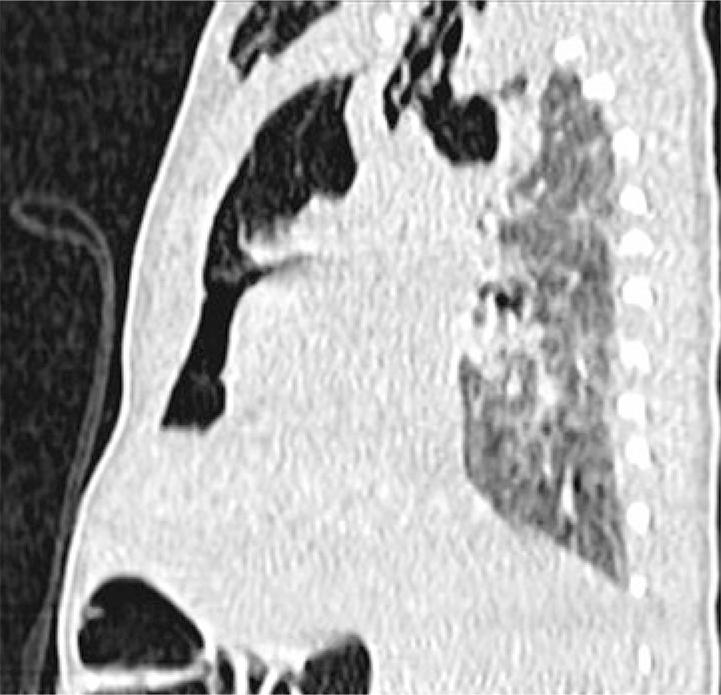

O exame radiológico apresentado pertence a um recém-nascido cuja gravidez foi vigiada e decorreu sem intercorrências. Nasceu por ventosa com 38 semanas, com choro imediato e índice de Apgar 9/10. Foi diagnosticado, no primeiro dia de vida, com enfisema subcutâneo na face anterossuperior do tórax. Efetuou uma radiografia de tórax que mostrou enfisema subcutâneo cervical e sinal de “vela de Spinnaker” (cunha hipotransparente estendendo-se até ao mediastino superior delimitada inferiormente por zona hipertransparente) (). Fez tomografia computorizada, que mostrou enfisema subcutâneo e extenso pneumomediastino, com discreta septação e sem alterações do parênquima pulmonar ( e ). O recém-nascido esteve sempre estável e apresentando boa evolução clínica. Controle radiológico no sétimo dia de vida sem alterações.